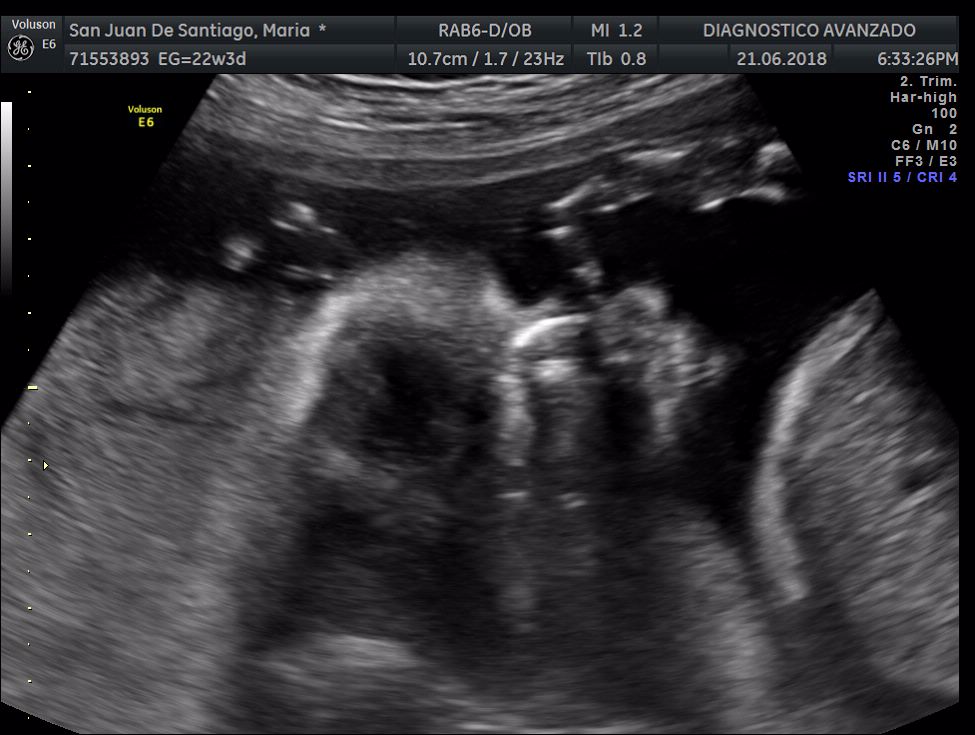

¡Hola a todos! Hoy hemos ido a hacer la tradicional ecografía 3D de la niña, os dejamos todo el material (aunque es un poco demasiado).